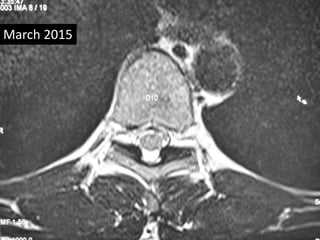

• Follow up MRI was done March 2015

• Complete absorption of fragmant.

March 2015

D10 – D11

D11